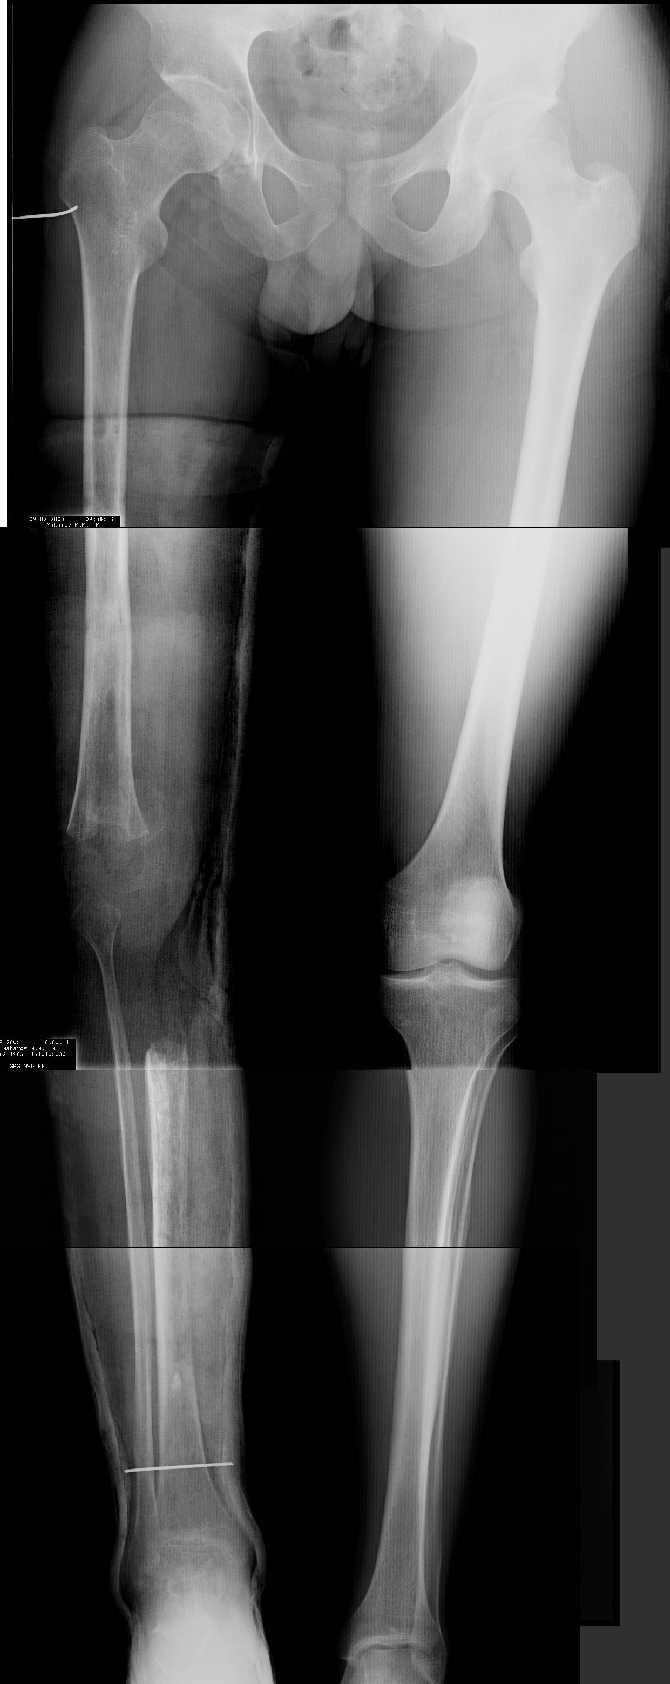

AV> многооскольчатый перелом правой бедреннойљ кости на границе

AV> средней и нижней трети со смещением,

AV> В настоящее время стойкая разгибательная контрактура правого

AV> коленного сустава (сгибание 105-110 гр., разгибание 160-165 гр.),

AV> варусная деформация, болевой синдром.

имеется S-образная деформация бедра на фоне "многооскольчатого

перелома правой бедреннойљ кости на границе средней и нижней трети со смещением"

(хотя "длинные" снимки конечно же не помешали бы...)

Почему же не вмешаться на в/3 голени (вальгизировать)?

По крайней мере это не усугубит контрактуры в коленном суставе но

позволит нормально перераспределить нагрузку...

На представленных снимках эта деформация как раз и не представлена.

1. Иллюстрации - во вложении.

Два бедра после эндопротезирования.

Авторы операции долго думали почему больная хромает.

Сдклали снимок - одна нога короче почти на 3 см.